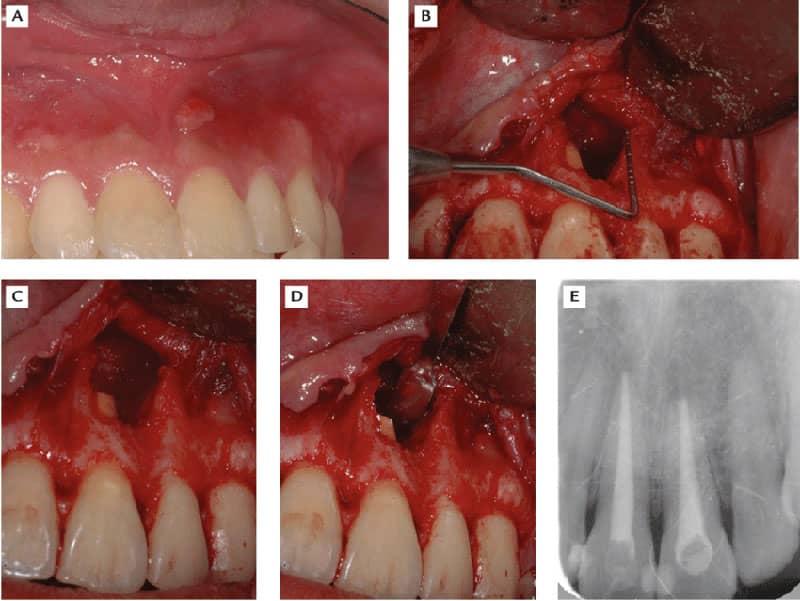

روش جراحی ریشه یا همان اپیکوسرجری چه موقع انجام می شود

در تمام موارد نمی توان با تخریب جزیی از تاج دندان پالپ را به صورت کامل خارج کرد و اتصالات عروق عصبی آن را قطع کرد. در چنین شرایطی نیاز است که با روش جراحی ریشه یا همان اپیکوسرجری، یک برش کوچک روی لثه ایجاد کرد و باقی مانده انتهایی ریشه و عفونت ایجاد شده را خارج کرد. در نهایت مانند مراحل درمان ریشه دندان، فرآیند شستشو و پر کردن انجام می گیرد.

گاهی ممکن است میزان عفونت بسیار زیاد باشد که همراه با خود، تورم و درد شدیدی را ایجاد کند. در چنین مواردی معمولا توسط دندانپزشک ابتدا آنتی بیوتیک آموکسی سیلین و مترونیدازول تجویز می شود. فرد باید با دقت داروهای تجویزی را مصرف کند تا شرایط برای انجام جراحی یا همان اپیکوسرجری مناسب باشد.